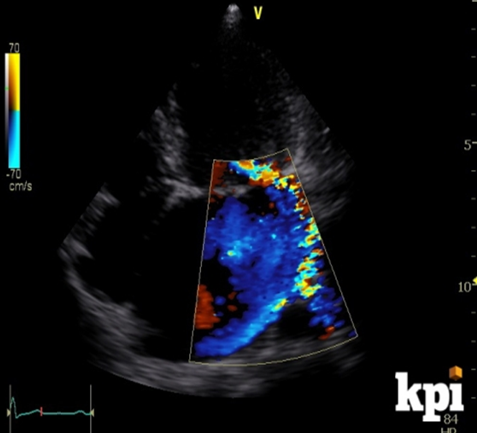

what is this?

eccentric regurgitant

how to assess for prosthetic paravalv regurg/periannular leakage?

color doppler